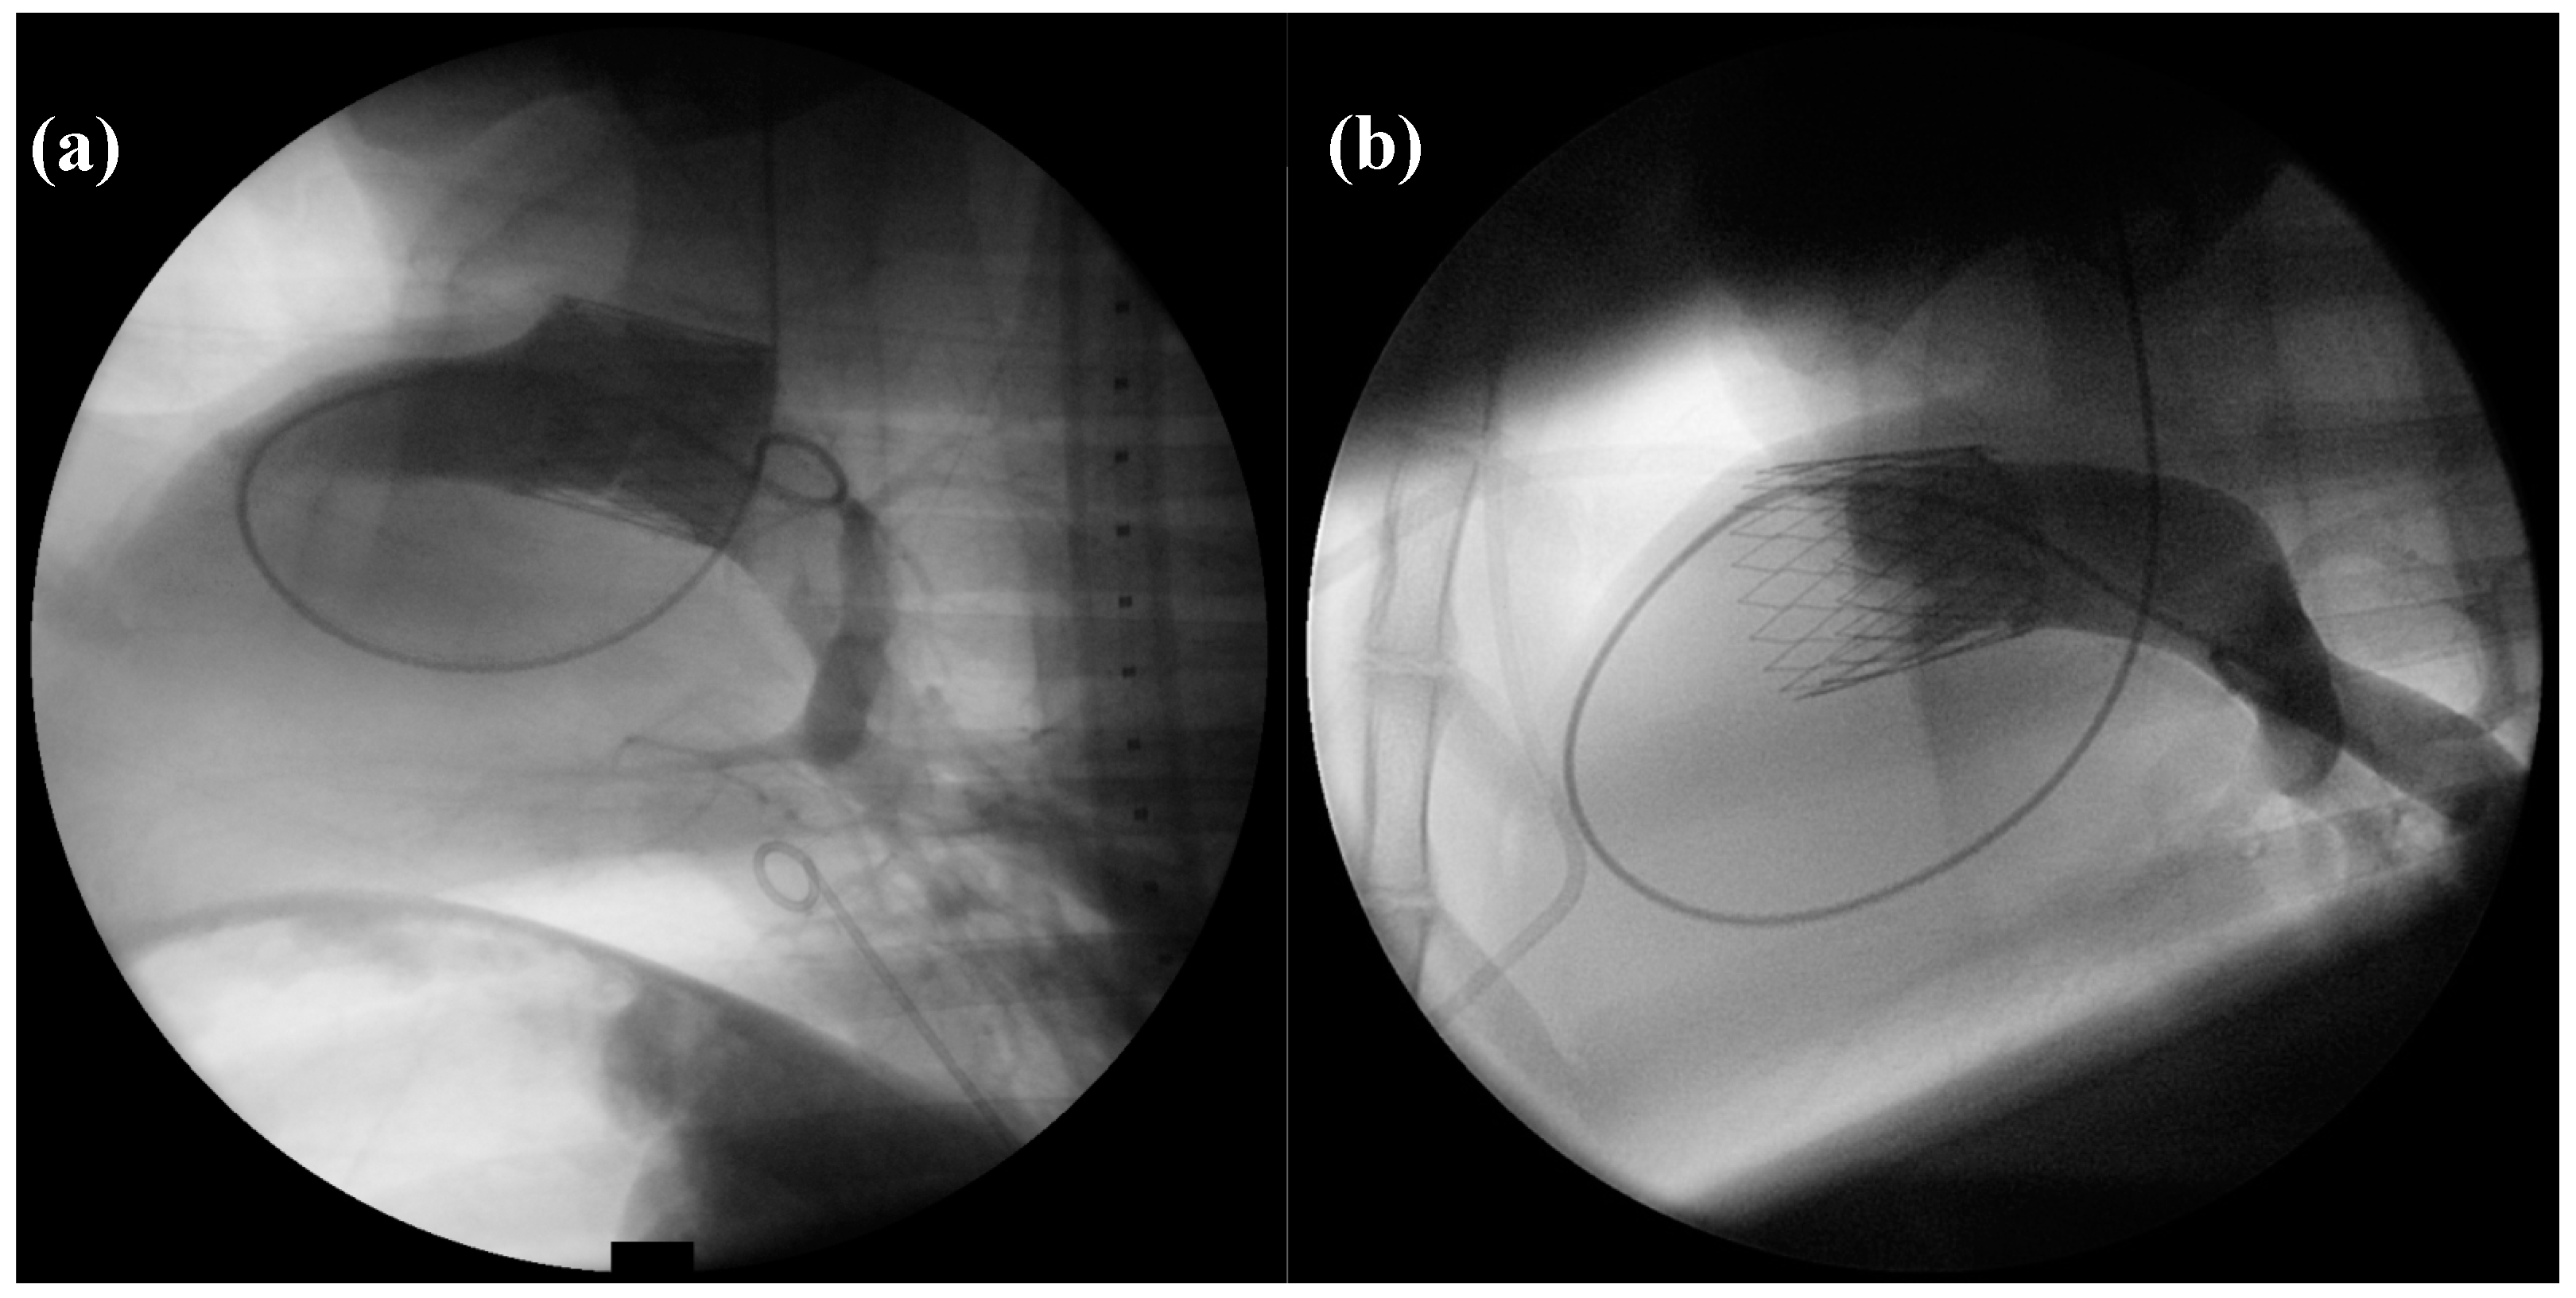

2.2. Angiography

Directly after implantation, 6 out of 15 (40%) dTEHV 1 showed sufficient valve closure during angiography of the pulmonary artery. Eight out 15 (53.3%) showed slight regurgitation of the applied contrast medium into the RVOT. In one case (7.8%), strong regurgitation with contrast medium staining the whole RV was seen.

All dTEHV 2 showed sufficient closing function in angiography directly after implantation. No contrast medium regurgitated into the RVOT or right ventricle. No paravalvular leakage was recorded either (Figure 4).

Figure 4.

PA-angiography with the application of contrast medium directly after implantation of the dTEHV (Left: First generation dTEHV; right: Second generation dTEHV). (a) Insufficient closure of the newly implanted dTEHV 1—contrast medium regurgitates back into the RVOT; (b) Sufficient closure of the newly implanted dTEHV 2—no contrast medium regurgitates back into the RVOT or RV. Even the belly-shaped leaflets can be seen in the picture.